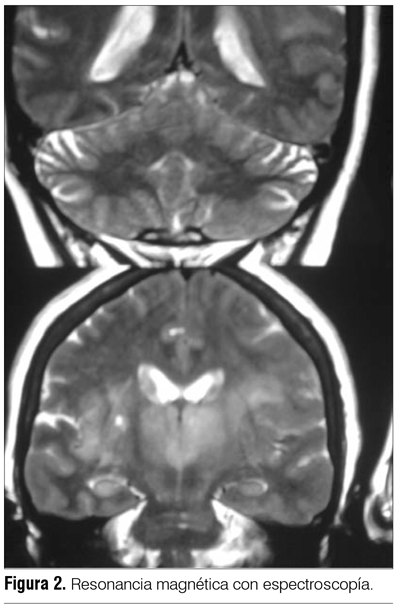

Reingresa al mes por cuadro similar requiriendo IOT por depresión de conciencia, realizándose nueva RM de cráneo que informa probable primitivo infiltrante del sistema nervioso central (SNC) (figura 1).

Se inicia tratamiento en base a dexametasona y difenilhidantoina. Se plantea biopsia estereotáxica que informa glioma de bajo grado, que por lo extenso de la lesión desde el punto de vista imagenólogico impresiona corresponder a la variante gliomatosis.

La tomografía de cráneo suele ser normal. En ambos casos el diagnóstico se realizó mediante RM, sabiendo que existe una disociación clínico-radiológica, de manera que la extensión de la lesión por neuroimagen es mayor que la repercusión clínica(1).